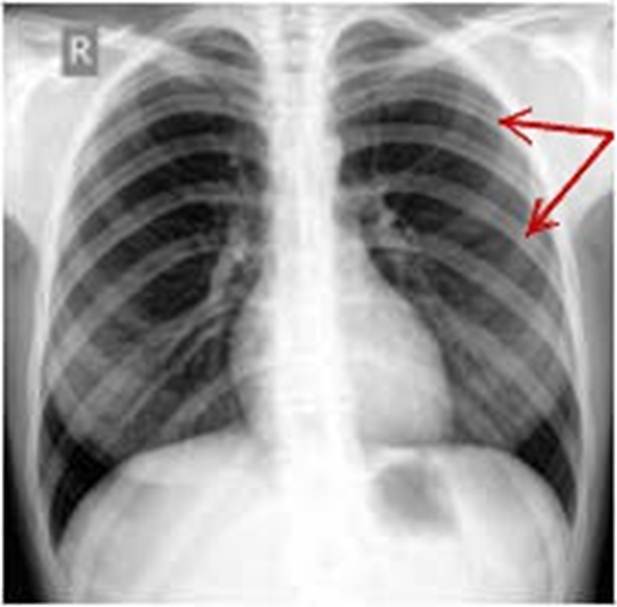

S: Стрелки указывают на сostae spuriae (латинский язык).